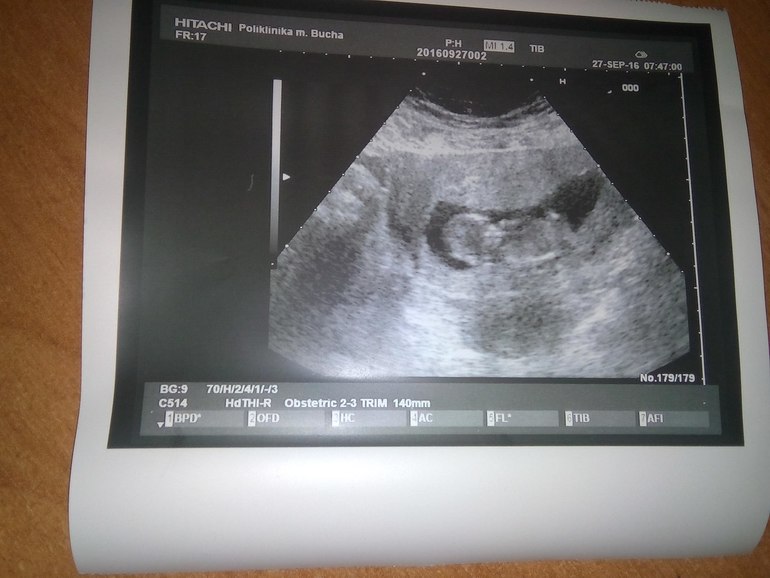

У нас получилось! Я беременна!Итак что имеем!? Сходила на УЗИ сегодня и у нас все хорошо))Лялька у нас одна соответствует сроку 13 недель сердечко бъется ручки ножки все хорошо))Конечно не сказали кто будет(Будем ждать!УЗИ делала в ЖК быстро конечно но даже фотку дали чему я очень рада)И наконец то увидела что там в животике действительно кто то живет!Такой милаха)